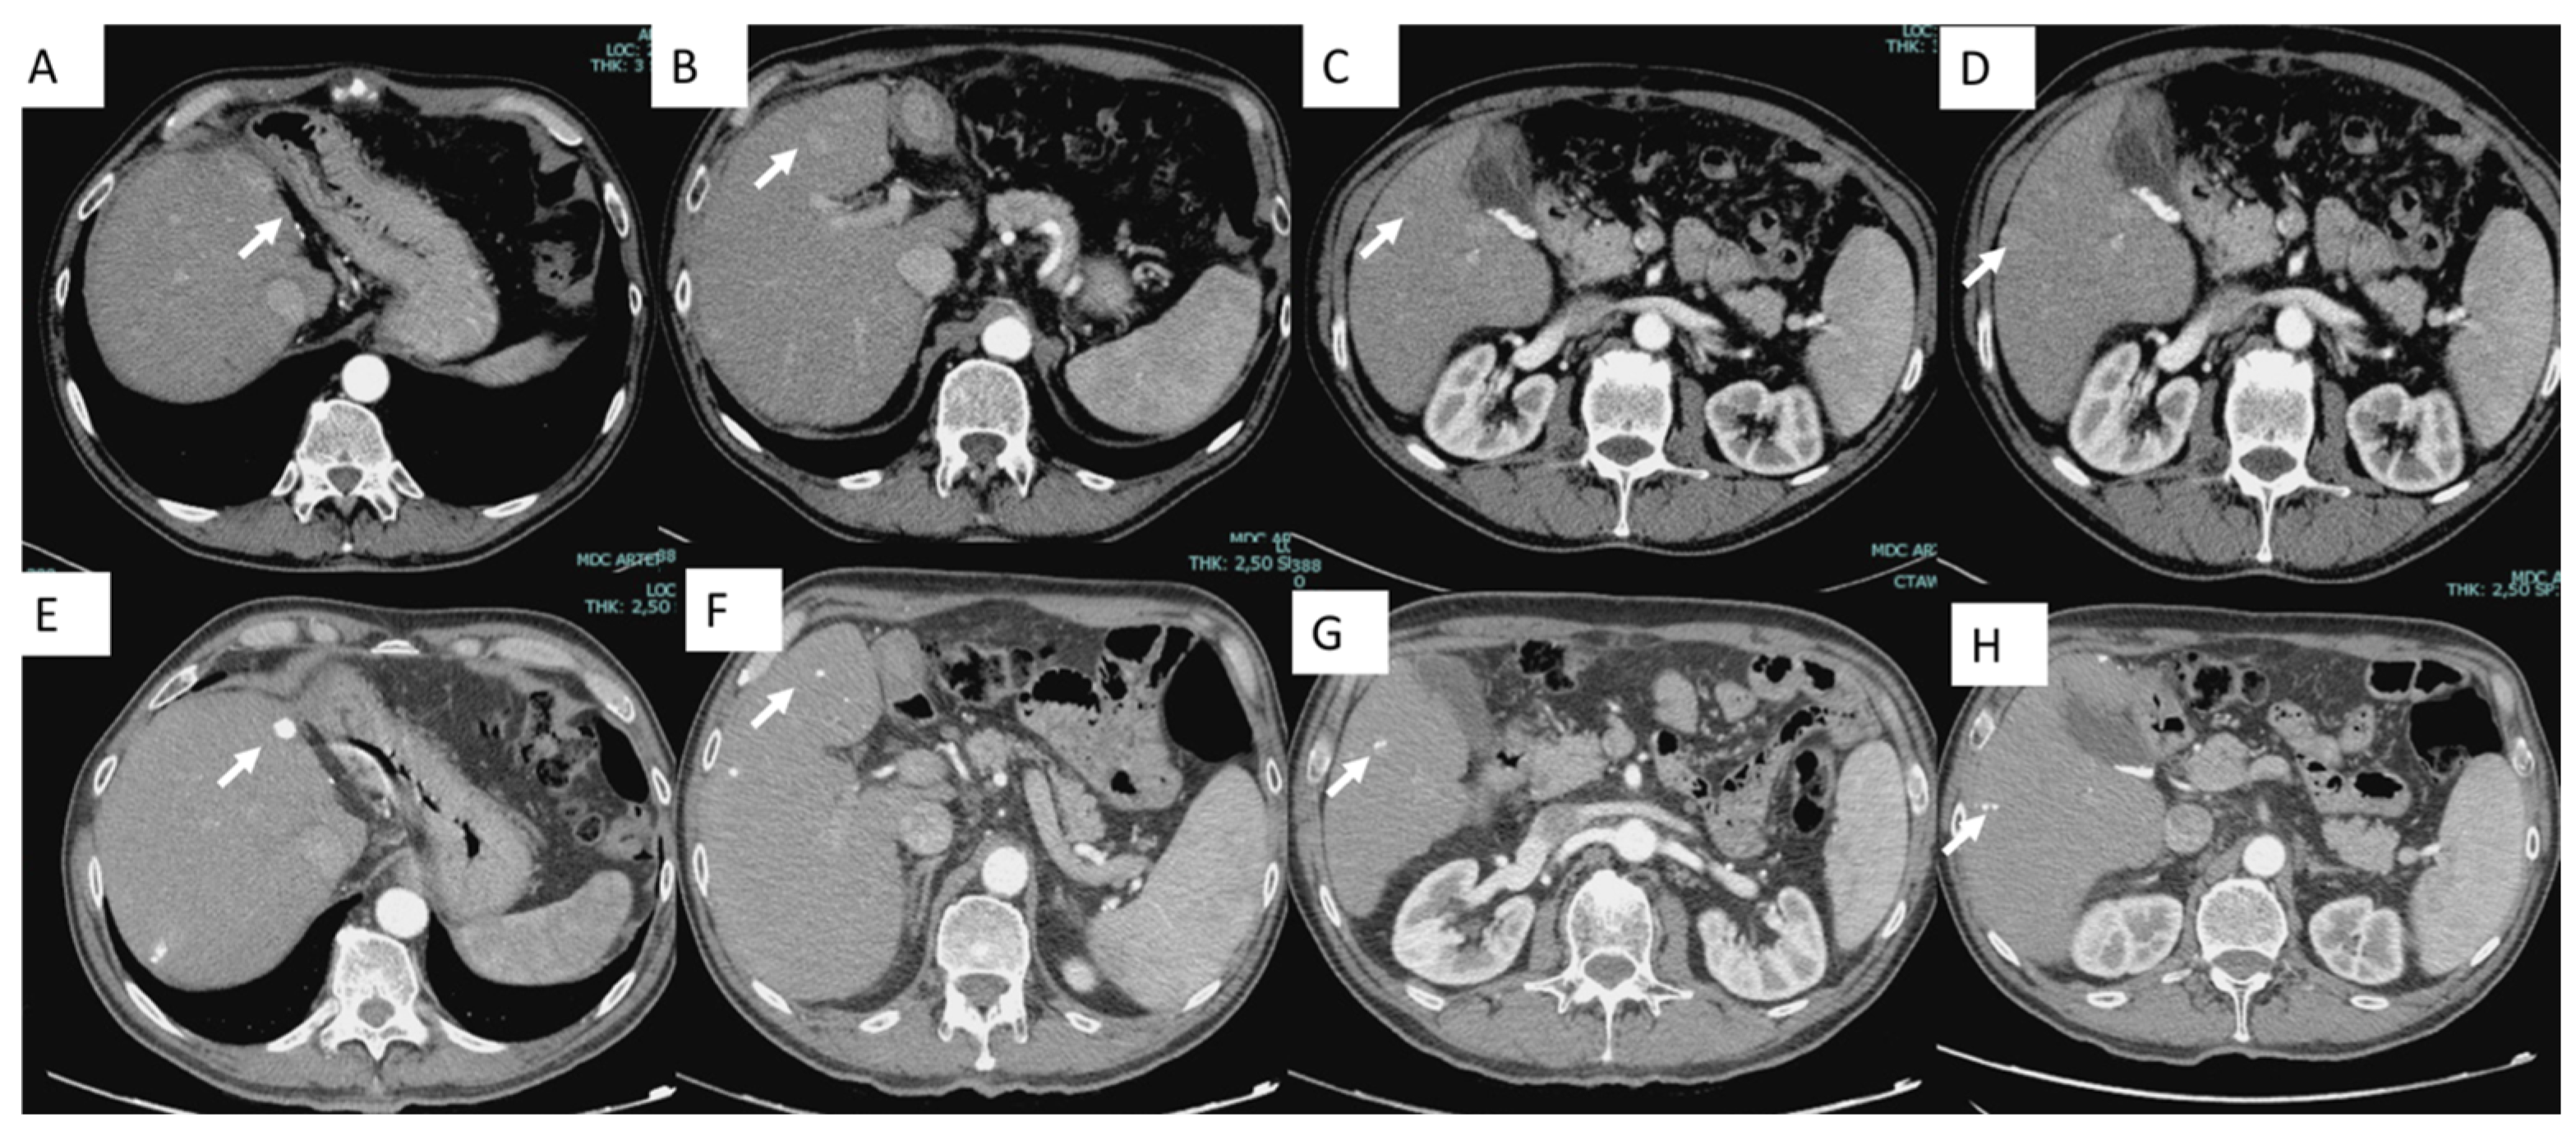

- Lucatelli, P.; De Rubeis, G.; Corradini, L.G.; Basilico, F.; Di Martino, M.; Lai, Q.; Corradini, S.G.; Cannavale, A.; Nardis, P.G.; Corona, M.; et al. Intra-procedural dual phase cone beam computed tomography has a better diagnostic accuracy over pre-procedural MRI and MDCT in detection and characterization of HCC in cirrhotic patients undergoing TACE procedure. Eur. J. Radiol. 2020, 124, 108806. [Google Scholar] [CrossRef]